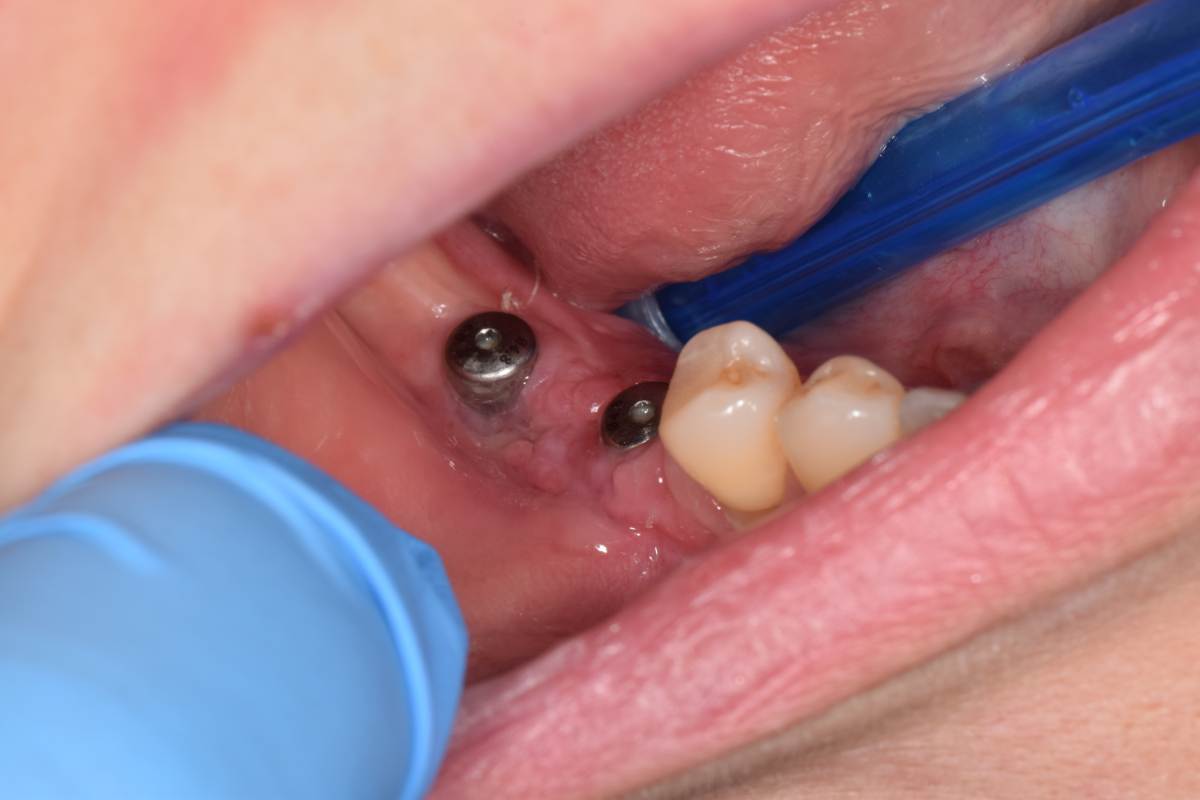

Да, фото есть. Но вспоминаю клин случай, там на первом этапе уже были проблемы.

СдТ по Едранову, видимо получил воспалительный процесс. В результате СДТ усело более чем на 50%.  Потом через 1.5 мес. открытие имплантов и ССТ. Некроз у одного импланта.Думаю связано с неполным ушиванием и ССТ с эпителием. Восстановление слизистой после некроза 2 мес и временное протезирование. Сейчас все выглядит достойно, но лишние нервы.

DSC_0905.JPG.d80af1f969af81edaec8fcb8e56af9dd.JPGDSC_0918.JPG.8053b3712edc335c60fe1603758c57c0.JPGDSC_0961.JPG.d7322462935746ed55516c1f2f016178.JPGDSC_1033.JPG.4e248180e536c308f43b21f90c8d7f39.JPGIMG_20250429_233136.jpg.c4afee93d2d2d38c68fd0335f7814cf2.jpgIMG_20250429_233013.jpg.58a7d5dc49b818431505d37c6561f01e.jpgDSC_0468(1)_d4542c.JPG.507134270c79baa6b79b4eb40f621175.JPG